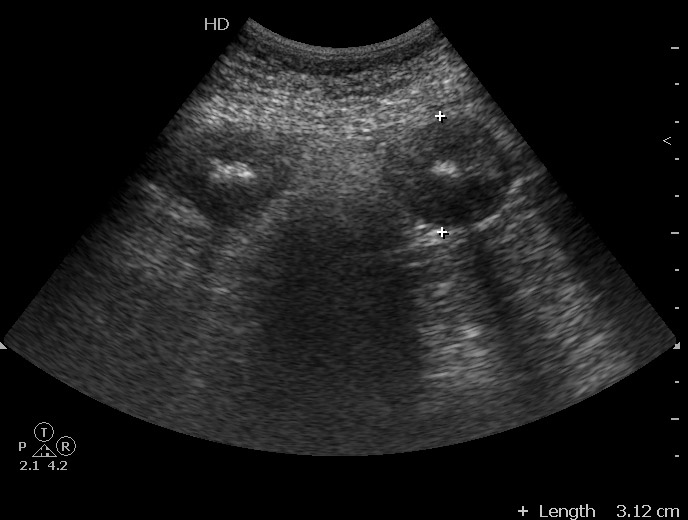

Молодая женщина, 36 лет.

Три дня назад поступила с жалобами на боли в животе в эпигастральной области. При УЗИ в БП небольшое количество жидкости - в малом тазу.

Аппендицит клинически исключен.

Повторный осмотр в связи с усилением болей в животе, появлением инфильтрата в эпигастральной области, снижением гемоглобина.

При УЗИ патологии печени, ЖП, панкреас, селезенки, почек не выявлено, имеется примерно прежнее количество свободной жидкости плюс изменения тонкой кишки:

При операции выявлен сегментарный тромбоз вен брыжейки тонкой кишки с некрозом петель.

В протоколе детальное описание изменений.

Заключение: Изменения стенок тонкой кишки. Свободная жидкость в брюшной полости.